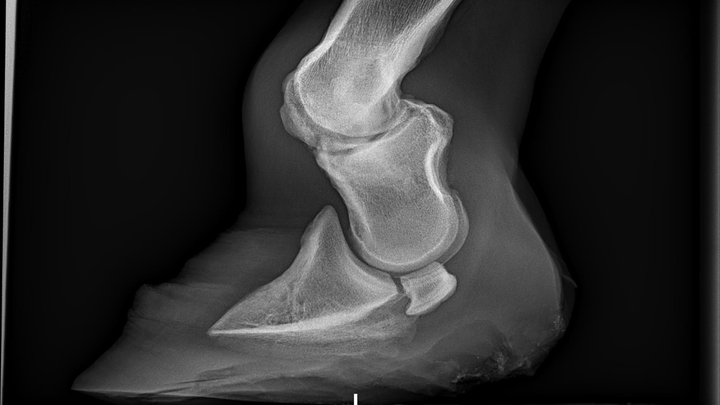

This is Phin my 11 month old colt i got from a slaughter holding pen in New York. He has a lige threatening bone deformity that needs operated on immediately. His date of surgery is December 18th and i got informed last week. After countless hours of phone calls with loan companies and banks this is my last resort. I have to pay close to half of the surgery cost upfront on the day of drop off. (12/17) this gave me no time to save or prepare. If any friends or family want to help me out i would be so great-full. Since christmas is right around the corner i know money is tight. But if you are friends or family this would be an amazing christmas gift for me.